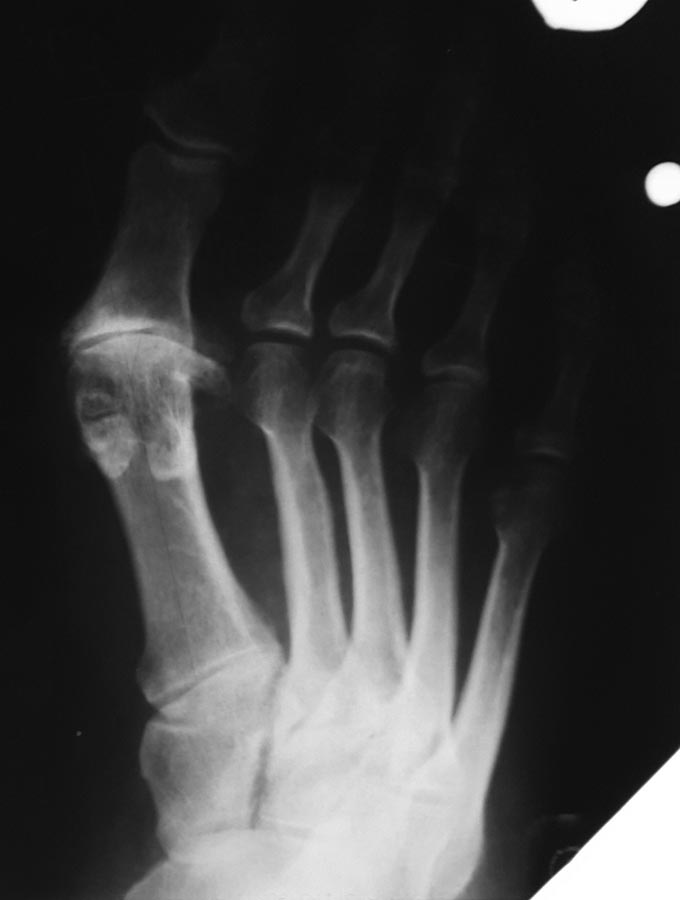

Фото до